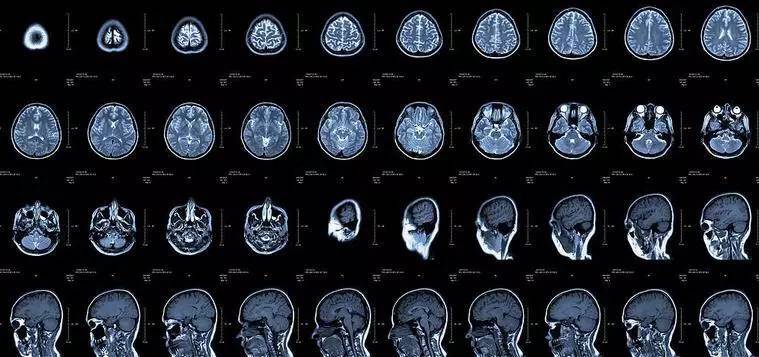

核磁共振:摇一摇再看

核磁共振机使用较强大的磁场,使人体中所有水分子磁场的磁力线方向一致,这时磁共振机的磁场突然消失,身体中水分子的磁力线方向,突然恢复到原来随意排列的状态。简单说就相当于用手摇一摇,让水分子振动起来,再平静下来,感受一下里面的振动。所以,核磁共振(MRI)也被戏说为是摇摇看的检查。